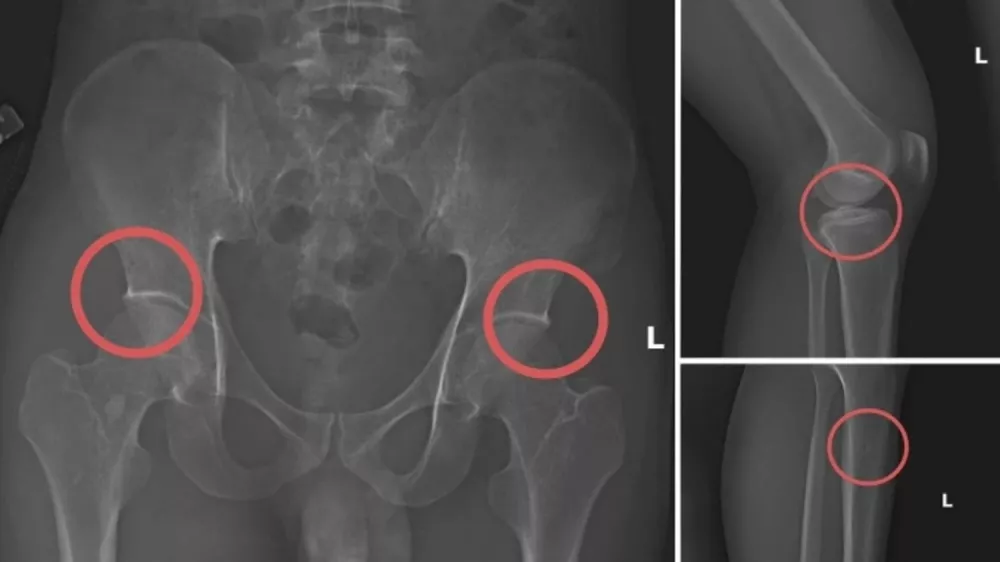

Preiskava je razkrila metodo, ki kaže na skrajno stopnjo preračunljivosti. Chau naj bi osebno izvajal posege. »Strankam je najprej vbrizgal anestetik, da bi preprečil bolečino,« je v izjavi navedla policija. »Nato je z brizgami in tesarskim kladivom povzročil zlome, zasnovane tako, da so bili videti popolnoma skladni s poškodbami iz resničnih nesreč.«

Da bi bila prevara popolna, so preostali člani združbe poskrbeli za lažno prizorišče. Pripravili so scenarije, kot je padec v potok, zdrs ali celo lažni udar elektrike. Združba je nato prevzela vso dokumentacijo, ponaredila zdravstvene kartoteke in vložila zahtevke pri zavarovalnicah.